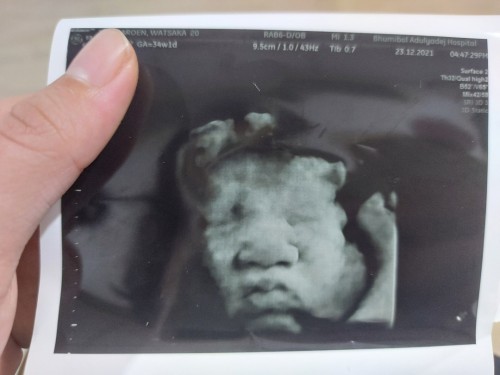

34+2วีคแล้วค่ะสาวอวบ🤣💓

Post reply image